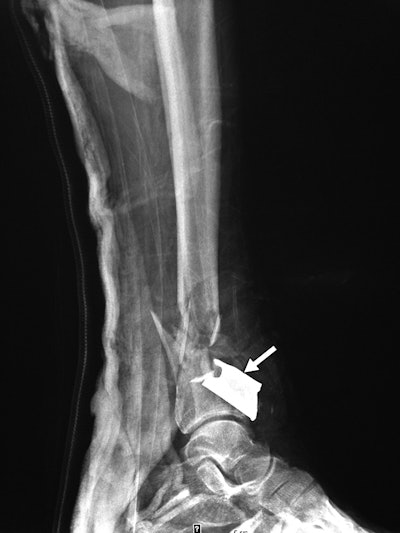

X-ray and CT showed a total of 189 shrapnel fragments in 32 (74%) of the 43 patients. Most of the objects (153, or 81%) were found in the soft tissues of the legs, thighs, and pelvis, while the remaining 19% were located above the pelvis or in the foot. The number of objects per patient ranged from one to 41 fragments.

Clinicians also found a large variety of debris embedded in patents. There were 125 ball bearings, 44 metal fragments, 10 nails, one screw, and nine pieces of gravel or other foreign objects. In addition, 11 patients had fractures in areas including the foot, leg, thigh, hand, orbit, nose, and lumbar spine. Injuries to five of the patients were so severe that they required lower-limb amputations.

Tertiary blast injuries result from falling or being thrown back by an explosion, according to the authors. In this category, right-sided lumbar transverse process and nasal bone fractures were found in two patients, along with a tibial shaft fracture in a third patient without any associated shrapnel or skin breech.